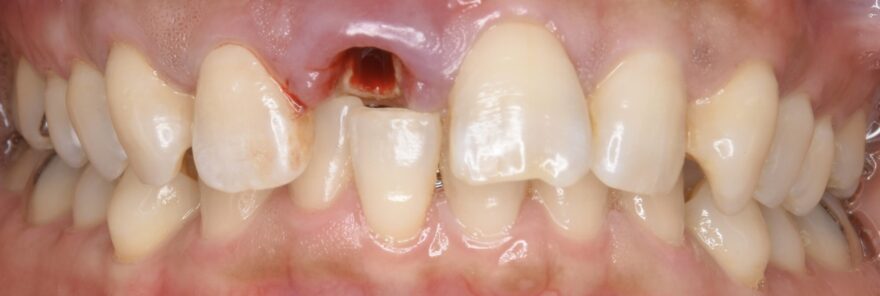

初診時の口腔内写真